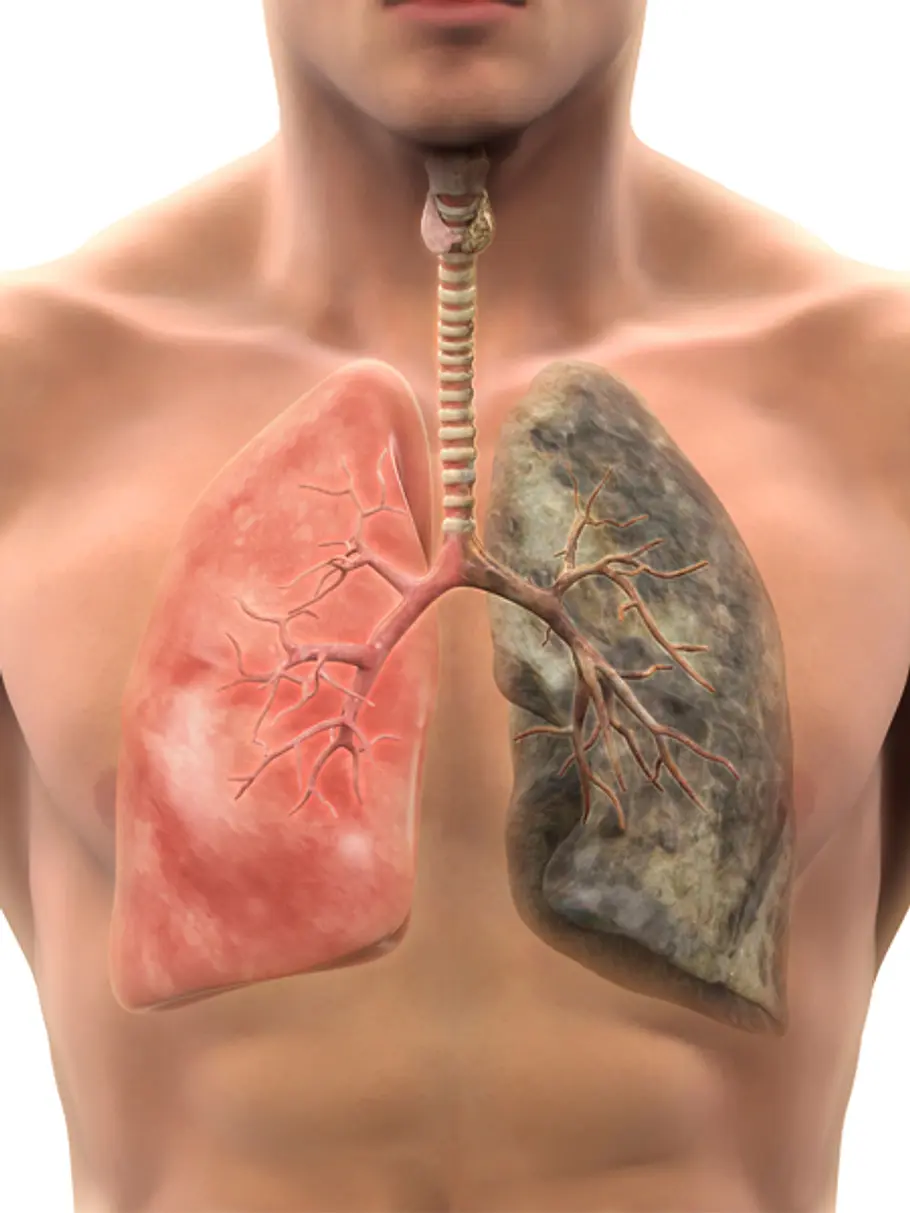

Raucherlunge

Die Raucherlunge oder auch COPD (chronic obstruktive pulmonary disease), wird oft unter der bekannten Bezeichnung des „Raucherhustens“ verharmlost. Unter diesem Krankheitsbild versteht man eine chronische Erkrankung der Lunge. Diese ist dabei dauerhaft entzündet und die Atemwege verengt, was zu Auswurf und Atemnot führt. Laut der WHO leiden 64 Millionen Menschen weltweit unter dieser Erkrankung und nimmt somit den vierten Platz der tödlichsten Krankheitenein.

Lungenemphysem

Natürlich zählen auch Atemwegserkrankungen, wie das Lungenemphysem, zu den häufigsten Raucherkrankheiten mit Todesfolge. Bei einem Emphysem kommt es zu bestimmten Abbauvorgängen, die die Lungenbläschen betreffen. Diese sind für einen funktionierenden Gasaustausch in der Lunge zuständig. Der Zigarettenrauch führt bei dieser Erkrankung dazu, dass die Bläschen beschädigt und im späteren Verlauf auch zerstört werden, worunter die Sauerstoffversorgung zunehmend leidet.